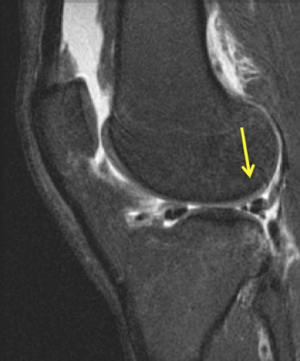

The most precise assessment of PCL injury is the posterior drawer test where, at 90 degrees of flexion, a posteriorly directed force is applied on the proximal tibia. In an uninjured knee, normally a step off anteriorly of 1 cm from the medial femoral condyle to the tibial plateau exists. The grading system mimics that of the ACL where grade I corresponds to translation of 1 to 5 mm while the normal step off remains. A grade II injury has 5 to 10 mm of translation and the condyle and plateau are flush, while grade III exhibits >10 mm of translation with the plateau being posterior to the condyle. This indicates a complete PCL tear. The posterior sag test, also known as Godfrey’s Test, evaluates this step off which is created by the tibial weight shifting the plateau posteriorly. The quadriceps activation test also is useful for evaluating PCL injury and is done with the knee at 60 degrees. During quadriceps activation, if a grade III tear exists, the tibia reduces anteriorly. The dial test is also essential to assess concomitant PLC injury, as the treatment and outcome will be different. Beyond concomitant ligamentous injury, evaluation of the menisci is essential. Careful and complete MRI review is important (Figure 7).

Figure 7 Sagittal MRI showing a Grade 2 posterior cruciate ligament (PCL) injury.